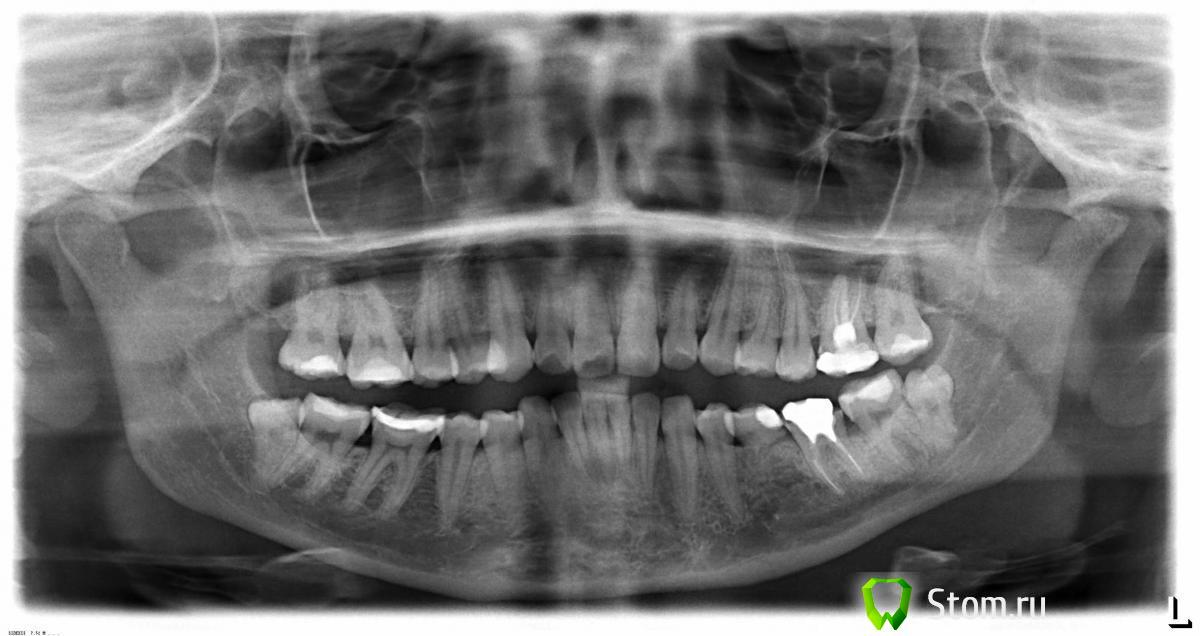

_m@xxi_ Опубликовано 15 апреля, 2012 Поделиться Опубликовано 15 апреля, 2012 здравствуйте, уважаемые участники форума! мне 25.04 предстоит удаление нижних восьмерок по показаниям (для ортодонтического лечения). потом предстоит удаление верхних четверок. до этого мне никогда не приходилось вырывать зубы. поэтому я очень-очень боюсь. попрошу Вашего мнения, насколько серьезна будет данная процедура. Насколько сложно будет удаление данных зубов в моей ситуации.Снимок прилагается.спасибо за ответы Ссылка на комментарий